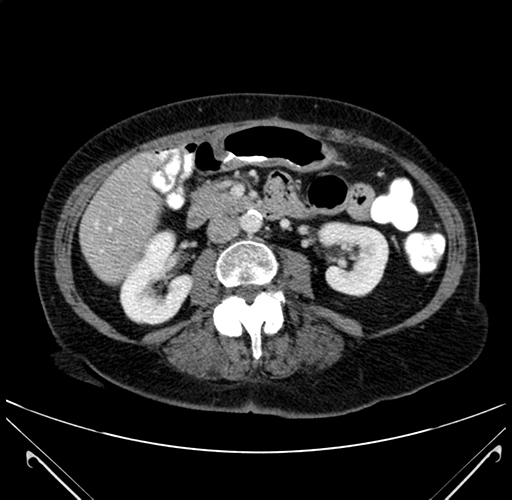

Coronal Venous